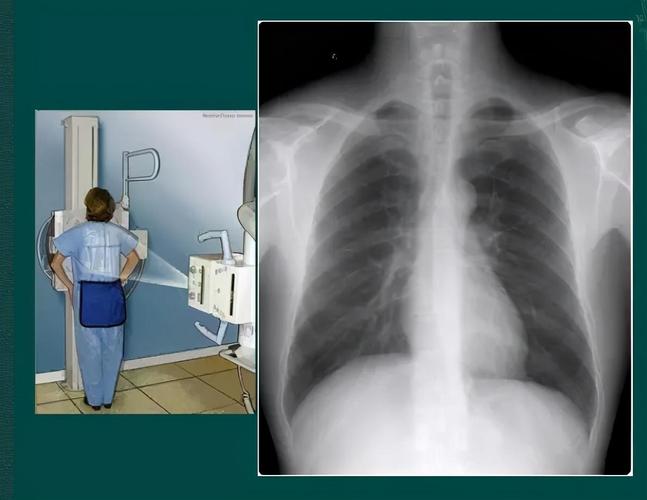

胸片检查,胸片胸透

正在做胸透拍胸片x光片的患者于检查人员这项检查几乎不需要特别准备.

正常胸片和异常胸片

正常胸片